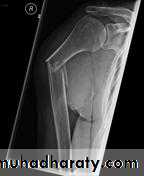

د.محمد الموسوي 12-10-2015Fracture shaft of humerus:

Traumatic & pathological3-5% of all fractures

Fracture location: proximal, middle or distal third.

Fracture pattern: spiral, transverse, comminuted or oblique.